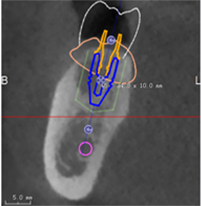

• CBCT第一次扫描(病人戴着放射导板)

• CBCT第二次扫描(单独扫描的放射导板影像)

第一次CBCT数据要求 :

• 患者戴着放射义齿拍摄,放射导板在口内与黏膜完全贴合密闭

• 除放射标记点外不得有任何金属物或阻射物

• 使用非阻射材料取咬合记录

• 保证咬合完全正确且稳定,无撬动及支点

3.添加放射导板数据

4.尽量让每一对匹配点角度一致

5.种植模拟设计